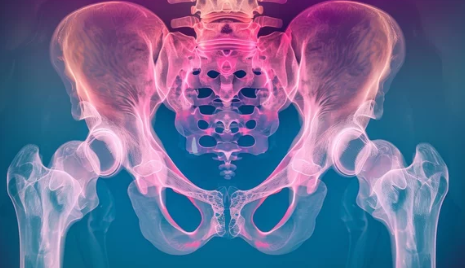

고관절(엉덩이 관절)은 신체의 중심부에 위치하여 하체의 움직임과 균형을 담당하는 중요한 관절입니다. 특히 노인의 경우 뼈가 약해지고 관절이 퇴행하면서 고관절 탈구(Hip Dislocation) 위험이 높아지며, 이는 일상생활에 큰 영향을 미칠 수 있습니다. 이번 글에서는 노인 고관절 탈구의 원인, 주요 증상, 치료 방법 및 예방법을 자세히 알아보겠습니다.

고관절 탈구는 엉덩이뼈(골반)와 허벅지뼈(대퇴골)가 연결된 관절에서 대퇴골두가 제자리에서 이탈하는 상태를 의미합니다. 이는 보통 강한 외부 충격이나 관절의 퇴행성 변화로 인해 발생합니다.